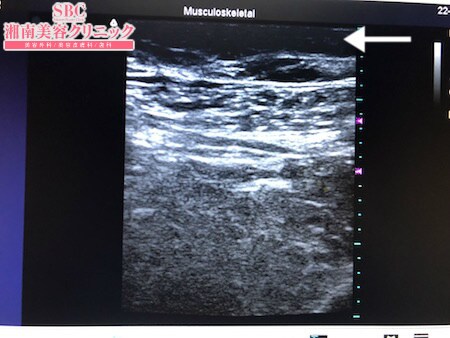

No.246707【脂肪吸引】【動画あり】湘南美容外科全ドクターの脂肪吸引最高責任者である竹田先生による脂肪吸引のフォトギャラリー!埼玉からご来院!二の腕の脂肪吸引に引き続き太ももを細くする!術中3Dタッチビュー・右太もも前面